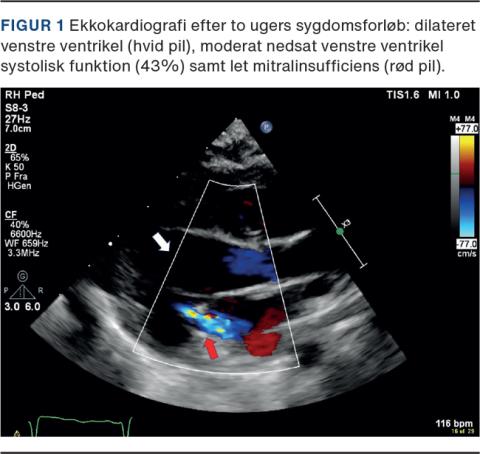

En 16 dage gammel dreng, som var født til termin ved vaginal fødsel og i god trivsel, var med sin familie på ferie i Norge. Han begyndte at melde sig mindre til måltiderne, havde enkelte opkastninger og blev tiltagende vejrtrækningsbesværet og bleg. En vagtlæge fandt drengen marmoreret med lav saturation og høj puls. Vædierne af hæmoglobin, blodsukker og C-reaktivt protein var inden for normalområdet. Han blev vurderet til at være cirkulatorisk dekompenseret, og der blev givet intraossøs væske. Han blev overflyttet til en neonatalafdeling, men blev i ambulancen ustabil og fik brug for støtteventilation og væskebolus flere gange. Ved ankomsten til sygehuset var han bleg og kold, og hans arterielle blodgas viste en svær metabolisk acidose trods respiratorisk kompensation, med pH på 7,05, pCO2 på 2,7 kPa, baseoverskud på –25 og laktat på 10,5 mmol/l, hvor middelarterietrykket var 45 mmHg, pulsen 160 slag/min og kapillærrespons 4-5 sekunder. Han udviklede bradykardi og klinisk hjertestop, og der blev påbegyndt avanceret genoplivning. Niveauet af pro-brain natriuretisk peptid var > 35,000 ng/l og troponin T var 1.018 ng/l. Ved ekkokardiografi (EKKO) blev der påvist strukturelt normalt hjerte, moderat nedsat venstre ventrikel-uddrivningsfraktion på 40%, svær mitralinsufficiens og pulmonal hypertension, hvilket var foreneligt med bl.a. myokarditis. Diagnosen enterovirusmyokarditis blev sandsynliggjort på baggrund af påvist enterovirus-RNA i blodet ved polymerasekædereaktion (PCR). Foruden kardiogent shock udviklede drengen kramper og sepsislignende tilstand med dissemineret intravaskulær koagulation. Han modtog relevant behandling for disse tilstande. Efter ca. to uger blev han overflyttet til Danmark, hvor der igen blev foretaget EKKO (Figur 1). Efter yderligere to uger blev han udskrevet i trivsel og uden tegn på sequelae ved efterfølgende kontrol.

Enterovirus, især coxsackie B-virus, er en af de hyppigste årsager til viral myokarditis [3]. Ved enterovirusinfektioner hos neonatale kan der ses feber, irritabilitet, sløvhed, spisevægring og udslæt. Det er således svært at adskille disse symptomer fra symptomerne ved bakteriel sepsis, og enterovirusinfektion bør derfor altid overvejes som differentialdiagnose, især i enterovirussæsonen (sommer/efterår) [1-5]. Myokarditis, herunder enterovirusmyokarditis, bør altid overvejes hos neonatale med hjertesvigtsymptomer eller -tegn, kardiomegali set på røntgenbilleder af thorax, belastningstegn set på elektrokardiogram, arytmi eller forhøjede myokardieenzymer [2, 3, 5]. Enterovirusinfektion diagnosticeres ved PCR-test af cerebrospinalvæske, blod, afføring eller luftvejssekret og har høj sensitivitet på > 90% [2]. EKKO kan støtte diagnosen enterovirusmyokarditis og viser ved svær myokarditis altid nedsat kontraktilitet af venstre ventrikel, dilateret venstre ventrikel og atrium samt mitral insufficiens [3, 5]. Tilstanden er sjælden, men hurtig progression kan ses med udvikling af shock, multiorgansvigt og pludselig død [3, 5]. Hos overlevende efter svær enterovirus-myokarditis ses både komplet remission og langsigtet morbiditet og sequelae, herunder arytmitendens, dilateret kardiomyopati og kronisk hjertesvigt pga. fibrosedannelse i myokardiet [2, 5]. For læger, som modtager nyfødte til vurdering, er det vigtigt at kende til myokarditisdiagnosen og ved gennemgang af luftveje, vejrtrækning og cirkulation (ABC) at kunne differentiere kardiogent shock fra andre shockformer, hvor især hepatomegali som tegn på øget preload tyder på kardiogent shock. Der er betydelig forskel på, hvilken initial behandling der skal gives ved kardiogent shock og andre shockformer, og bl.a. større væskeindgift vil forværre kardiogent shock yderligere, mens sedation anses som en højrisikoprocedure. Akut behandling af enterovirusmyokarditis består af ABC-stabilisering, symptomatisk behandling (inotropi, diuretika, respiratorbehandling), evt. intravenøst givet immunoglobulin, og ekstrakorporal membranoxygenering i tilfælde af kredsløbssvigt. Tidlig diagnose og symptomatisk behandling er afgørende for prognosen [3, 5].